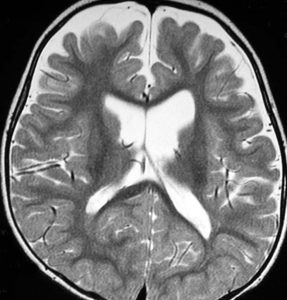

幼児期にgelastic seizureで発症

2歳でgelastic seizureを発症,6歳で思春期早発となりました

左視床下部に限局して柄を有するものです,左視索と乳頭体との境界はありません

おそらく左視床下部の機能低下と難治性の発作が原因で,左大脳半球の萎縮(あるいは発達不良)が認められます

予後がかなり不良だと判断して,2004年に摘出術をしました

術後のMRIです,pterional approach でしか摘出できない腫瘍でした

高い位置がとどかず少し取り残しました

gelastic seizureは減荷されましたが残り,術後に視野欠損を後遺しました

2019年時点でもこのよう過誤腫を治療することは困難です